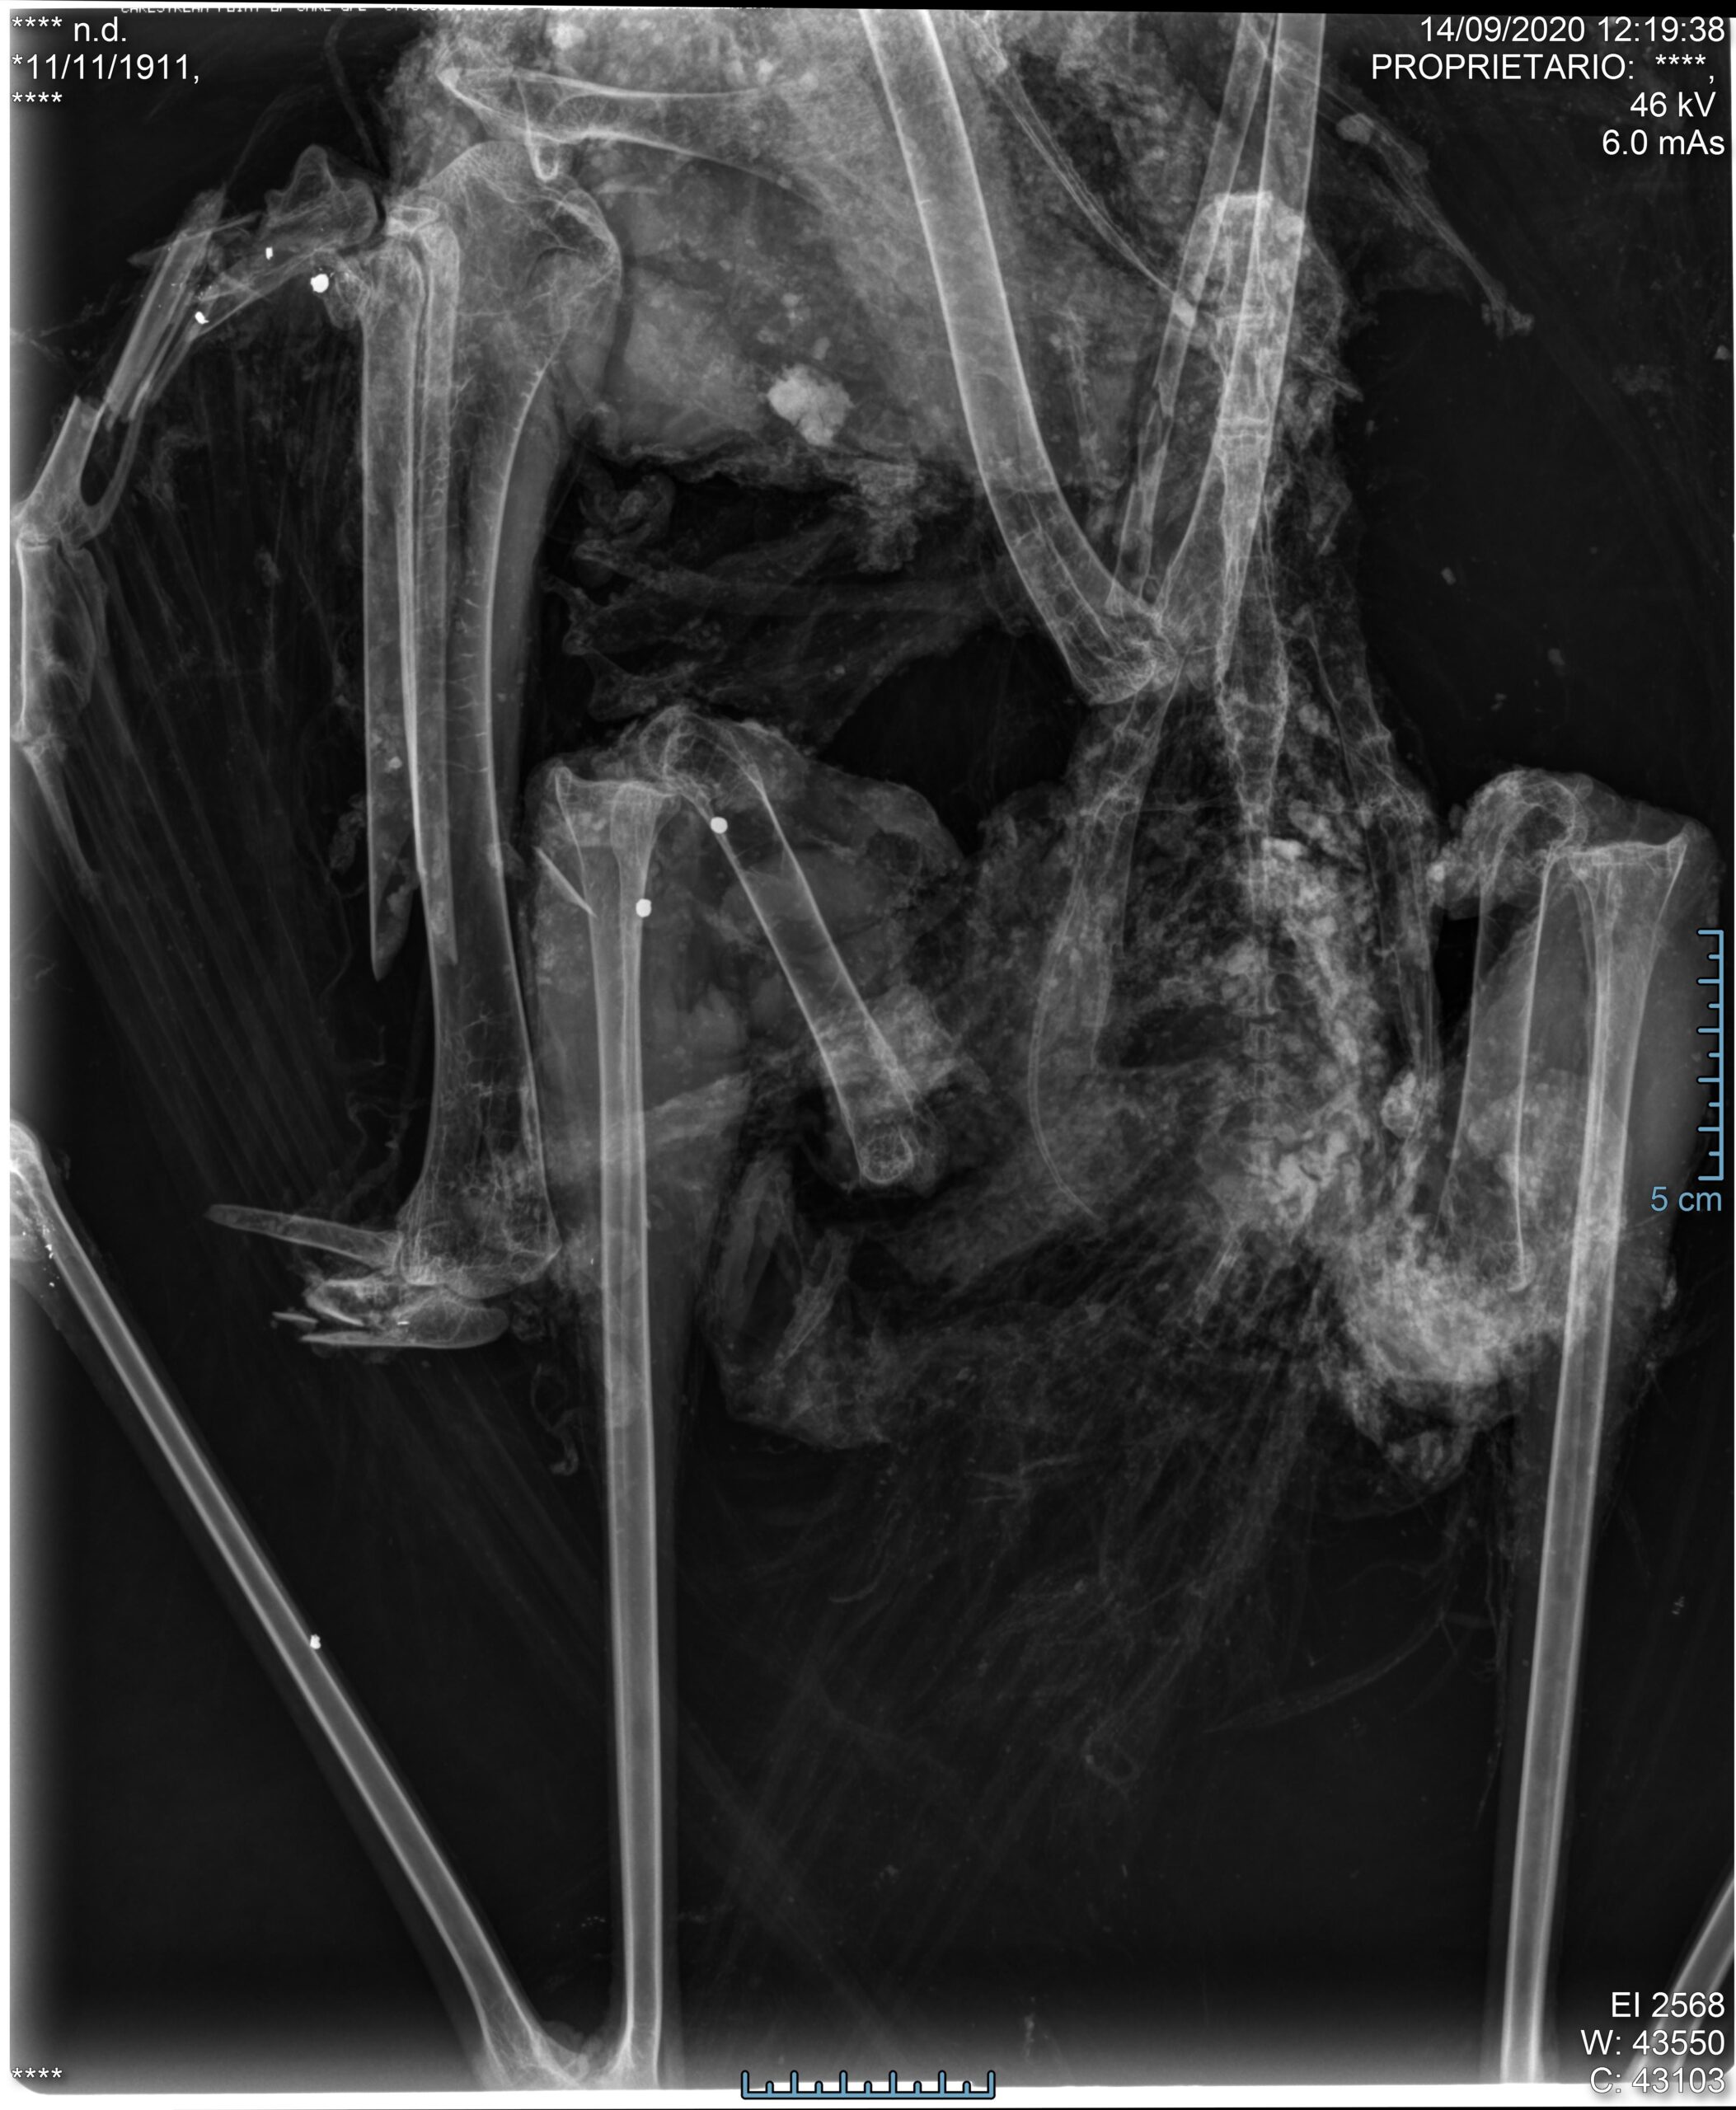

Il ritrovamento in provincia di Foggia di due rarissime Cicogne nere ormai morte, centrate dai pallini da caccia, rappresenta solo l’ultimo esempio di un lungo elenco di animali appartenenti a specie particolarmente protette uccise nel mese di settembre.

La Cicogna nera è un animale molto raro che solo di recente ha iniziato a ricostituire una piccola popolazione nidificante con pochissime coppie in Italia. Ogni animale in meno è un attentato alla biodiversità mondiale. “Un animale – ha aggiunto il CABS – che, per grandezza e colorazione, non può essere confuso con nessun altro”. In Puglia vi è poi uno dei sette blackspot del bracconaggio italiano, individuati proprio dall’inattuato “piano” redatto dal Ministero dell’Ambiente. Un fatto che dovrebbe imporre una maggiore attenzione sull’area, ma che, evidentemente, ha ignorato chi ha puntato il fucile contro i due poveri animali.